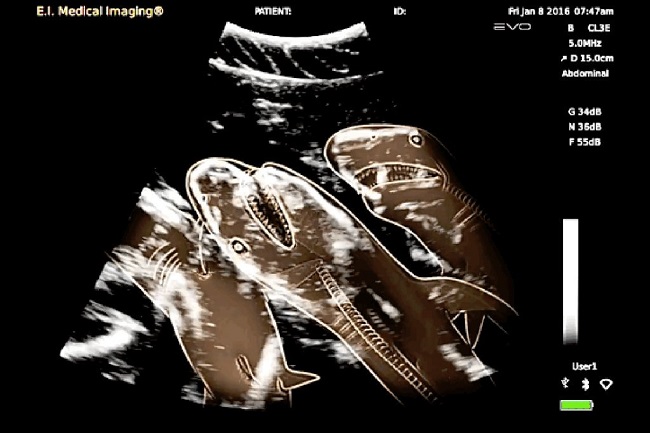

Sharks are the most difficult to study for obvious reasons and researchers have attempted for years. This is not to say they are beyond experiments, but they are just more inaccessible than other mammals. The above picture is thus, is not an x-ray but an ultrasound with drawn out lines which will help you understand their system.

Image Source: funnyjunk.com